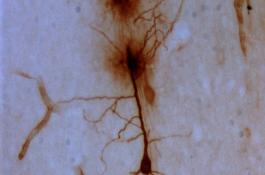

Investigadores del Instituto de Neurociencias, centro mixto del Consejo Superior de Investigaciones Científicas (CSIC) y la Universidad Miguel…